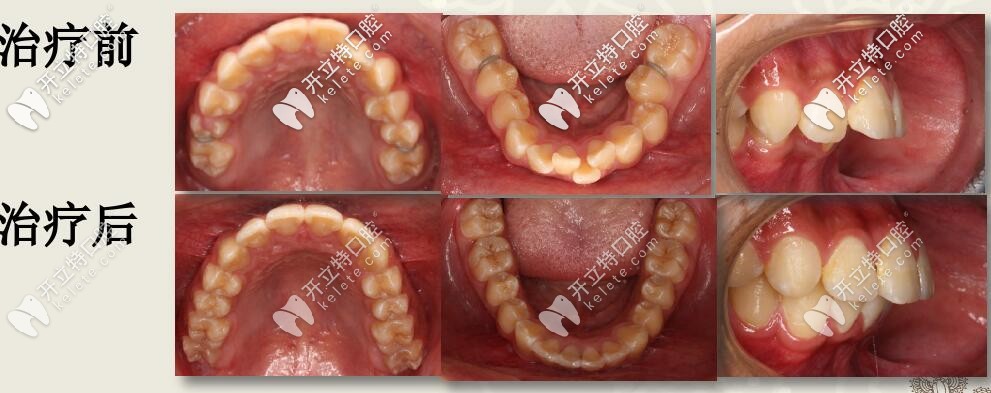

肉眼可見(jiàn)上前牙唇傾,輕度擁擠 下頜牙弓寬度窄,前牙區(qū)擁擠,后牙去舌傾明顯,前牙深覆蓋,深覆合

線圣貝口腔肌功能結(jié)合擴(kuò)弓矯治案例

圣貝口腔何曉天交之案例

先圣貝牙科牙齒矯正案例

結(jié)束后,牙列整齊,深復(fù)蓋明顯改善。